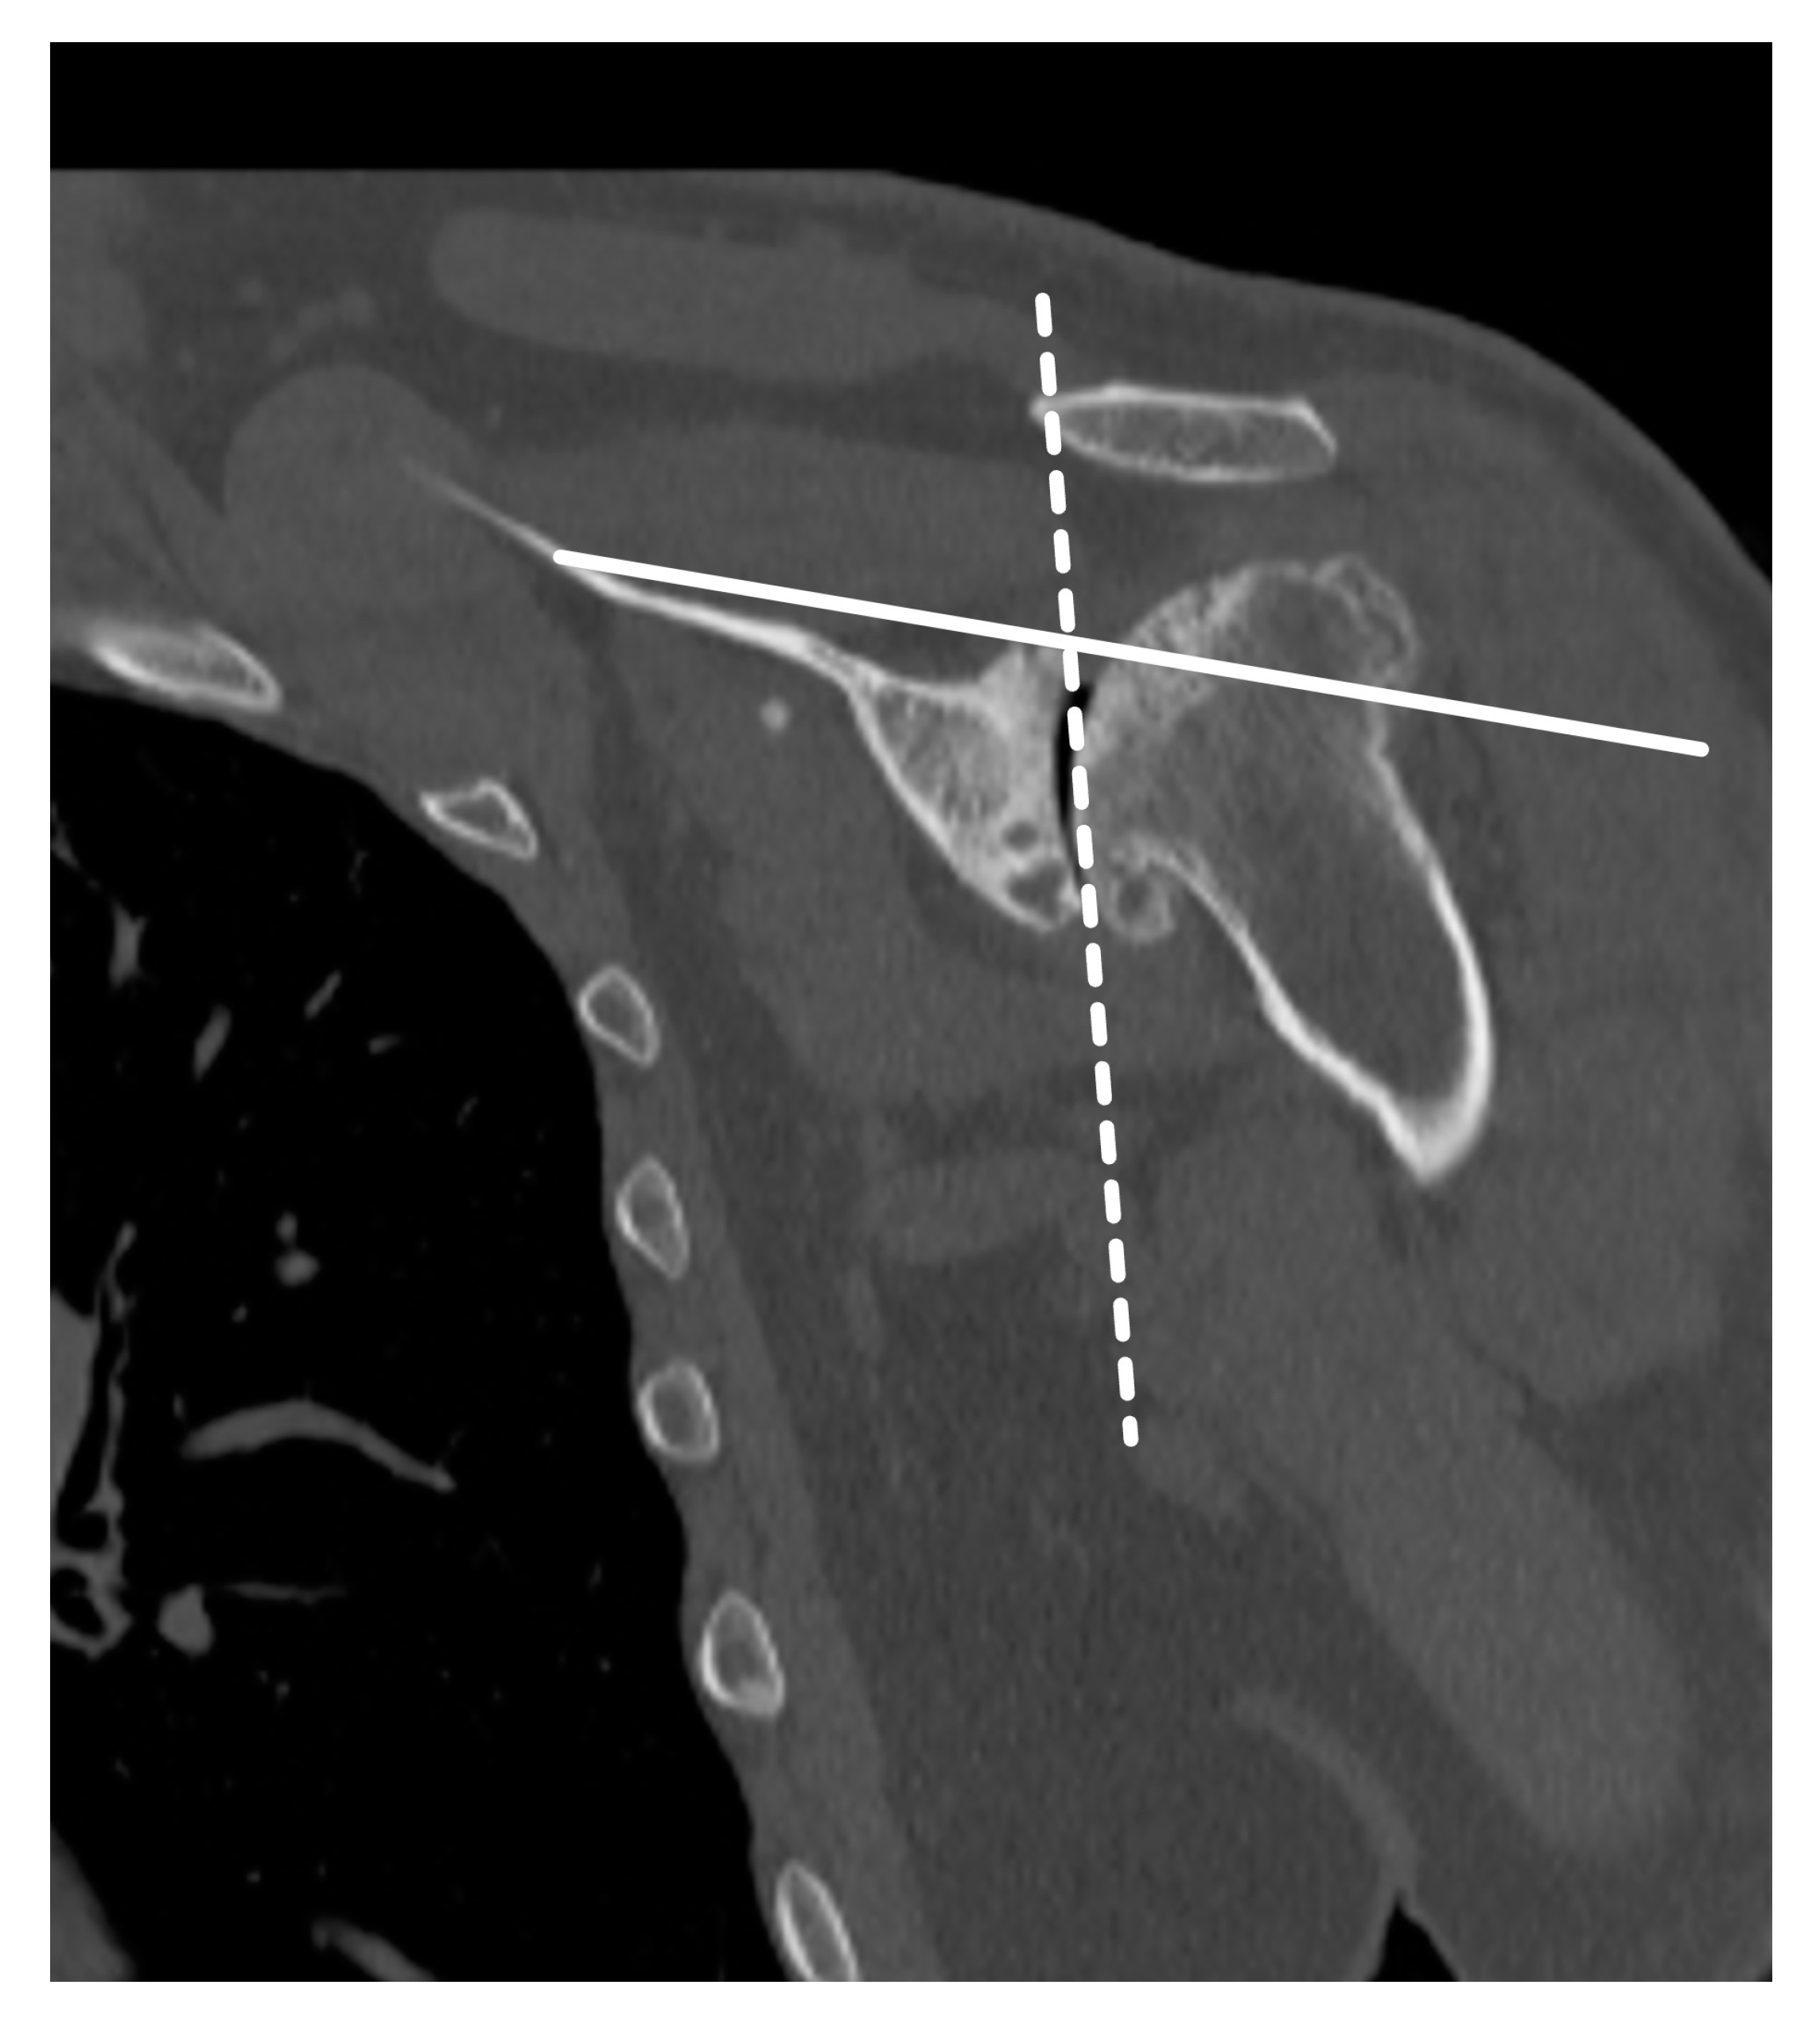

3. Preoperative Imaging

- Sharifi, A.; Siebert, M.J.; Chhabra, A. How to Measure Glenoid Bone Stock and Version and Why It Is Important: A Practical Guide. Radiographics 2020, 40, 1671–1683. [Google Scholar] [CrossRef]

- Walch, G.; Badet, R.; Boulahia, A.; Khoury, A. Morphologic study of the Glenoid in primary glenohumeral osteoarthritis. J. Arthroplast. 1999, 14, 756–760. [Google Scholar] [CrossRef] [PubMed]

- Bercik, M.J.; Kruse, K., 2nd; Yalizis, M.; Gauci, M.-O.; Chaoui, J.; Walch, G. A modification to the Walch classification of the glenoid in primary glenohumeral osteoarthritis using three-dimensional imaging. J. Shoulder Elb. Surg. 2016, 25, 1601–1606. [Google Scholar] [CrossRef]

- Budge, M.D.; Lewis, G.S.; Schaefer, E.; Coquia, S.; Flemming, D.J.; Armstrong, A.D. Comparison of standard two-dimensional and three-dimensional corrected glenoid version measurements. J. Shoulder Elb. Surg. 2011, 20, 577–583. [Google Scholar] [CrossRef]